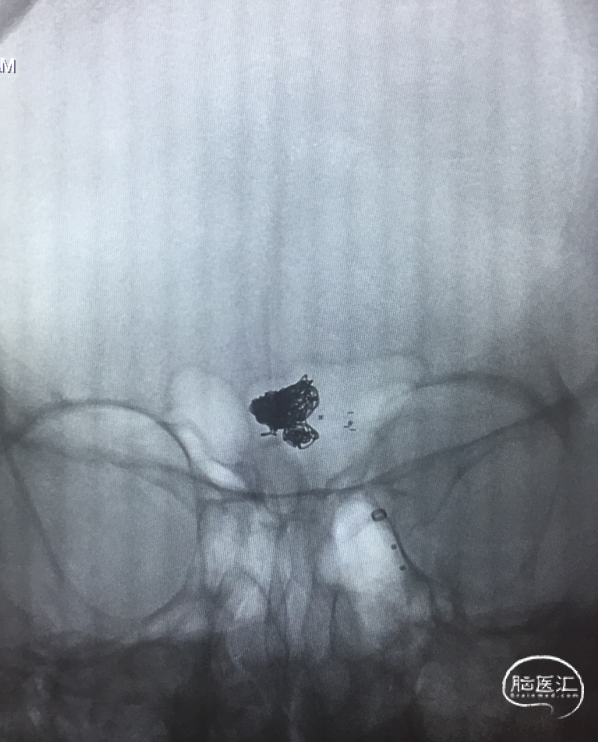

支架内球囊扩张

Synchro(200cm)携Echelon-10到达RACA A3(左图)。Synchro(300cm)交换Gateway1.5×9mm及Ultra-soft SV 2.0×20mm支架内扩张(6 atm)(右图)。